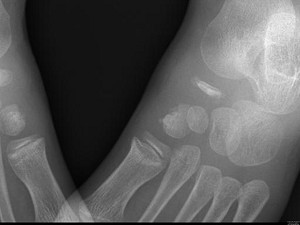

[单选题]男,28岁,踝部肿痛,结合图像,最可能的诊断是().A.未见异常B.跟骨骨髓炎C.踝关节滑膜炎D.跟骨结核E.踝关节类风湿关节炎